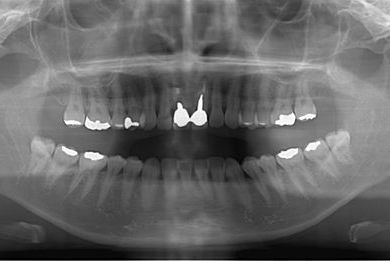

| 治療方針 | 上顎前歯、抜歯と同時にインプラントを埋入し、治療期間を短縮する。 | ||||||||||||||||||||||||||||||||

| 治療内容 | インプラント2本、メタルボンドセラミッククラウン2本 | ||||||||||||||||||||||||||||||||